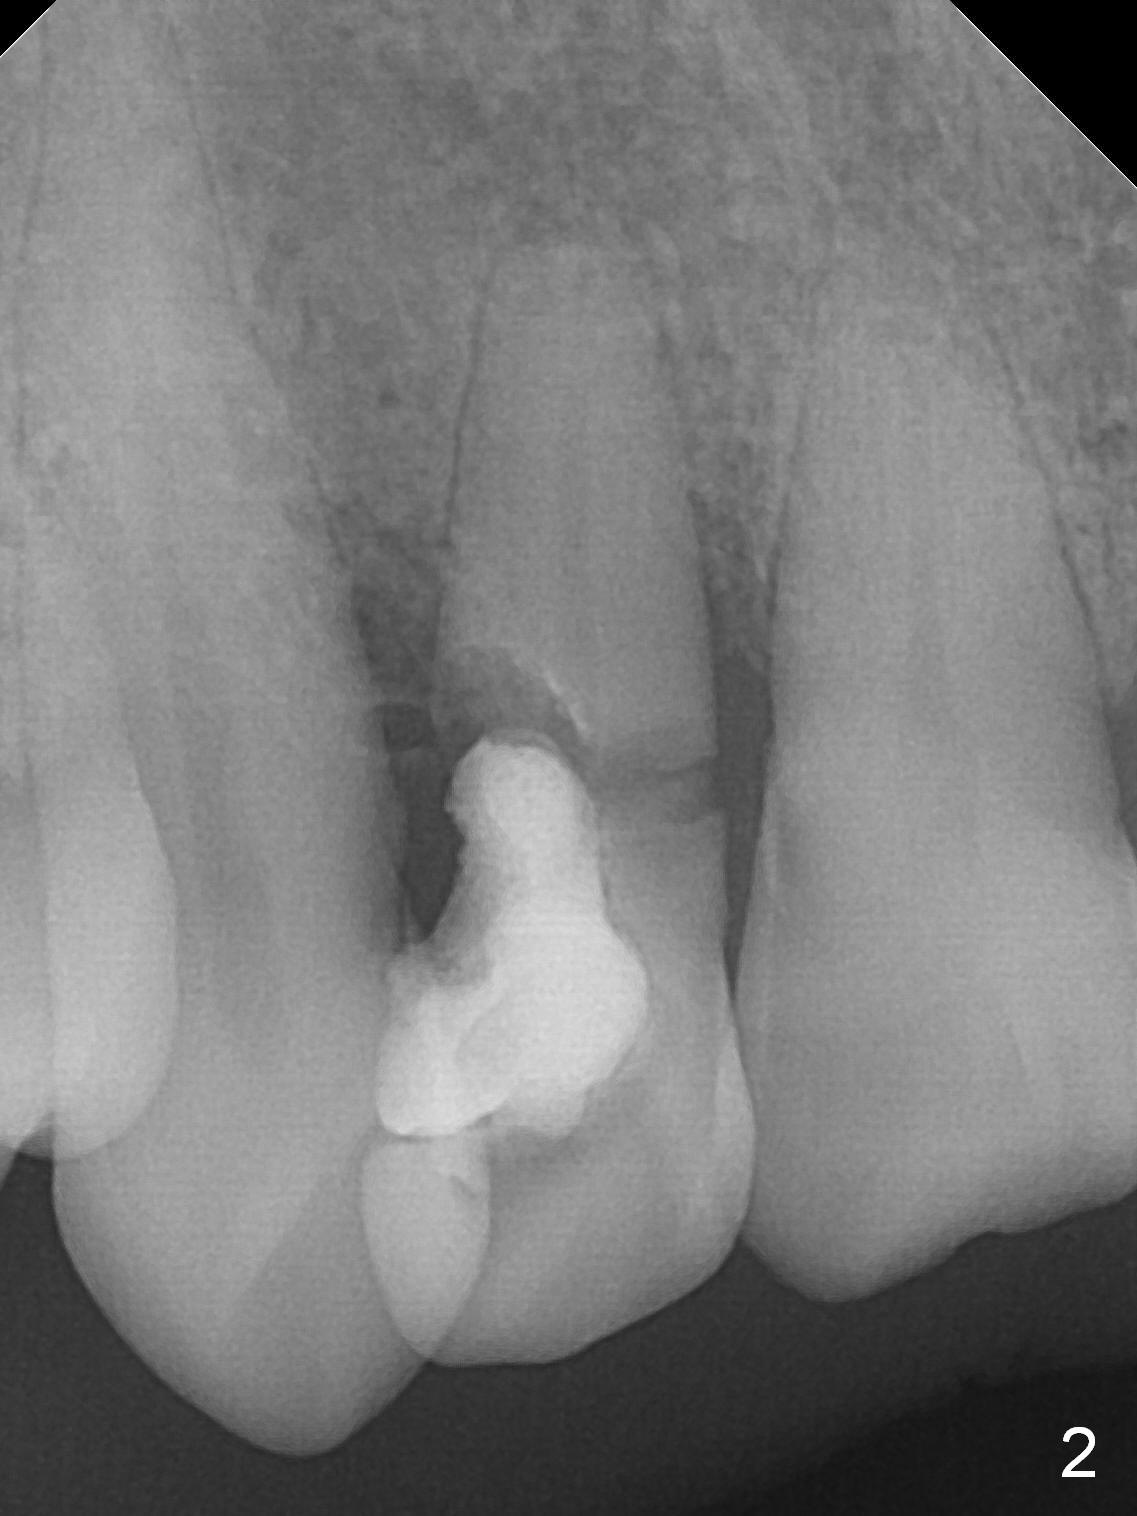

Root Fracture of Lateral Incisor with Possible Buccal Plate Defect

A 52-year-old man had a non-restorable lateral incisor 3 years ago (Fig.1). It fractures lately (Fig.2) with a buccal abscess (Fig.3 *) ) and fistula (>, possible severe buccal plate defect, prepare PRF). Severe deep bite (Fig.4) and malocclusion (Fig.5) will present a challenge to implant provisional restoration.